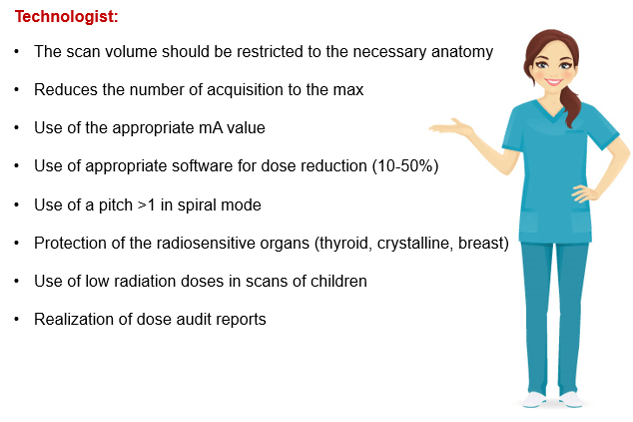

Many factors affect the dose in CT. Dose reduction, in addition to methods that were developed to account for the variation in patients, has been developed.

How the scan is performed can directly affect the dose deposited into the patient. Patient-specific factors include such factors as age, size, and sex play a role in deposited dosage. We need to discuss the absorbed dose, the delivered dose, and the effective dose.

While there are many stakeholders, such as the FDA and the NRC, who oversee patient and personnel safety, the first line of defense in the use of CT dose reduction is the individual facility. Radiologists, technologists, and physicists play an important role in reducing doses during scanning.

Since we have already reviewed the radiation physics involved with scanning, we will now describe how the patient dose is measured in a CT image or procedure and how this dose is affected by the value of the kV, mA, auto mA and pitch. A discussion of the reduction methods used will also help us to understand how to achieve quality images utilizing the lowest doses as possible. Remember, we must always keep ALARA in the back of our minds.

Patient Dose Reduction

The number of CT examinations in the United States has significantly increased in recent decades. The faster gantry rotation cycle times markedly reduced the need for anesthesia in children. In 2008, the Image Gently campaign was founded by the Society for Pediatric Radiology, the American Society of Radiologic Technologists, the American College of Radiology, and the American Association of Physicists in Medicine (AAPM) with the goal of increasing pediatric CT radiation dose awareness by starting a national education and awareness program.

Pediatric dose reduction is important for the safety of children. There are many practices recommended by the Alliance for Radiation Safety in Pediatric Imaging that reduce the dose to children. Such things as scanning only when necessary, reducing the radiation used, asking your medical physicists to monitor your CT techniques and not using multiphase scanning are all important components of pediatric scanning.

Adult Dose Reduction

In 2009, the American College of Radiology (ACR) and the Radiological Society of North America (RSNA) established the Joint Task Force on Adult Radiation Protection to address the safe and effective use of medical imaging and to incorporate dose optimization into all imaging practices Using dose optimization in scanning adults and geriatric patients is the radiation protection principle used to make sure that patient doses are kept as low as reasonably achievable (ALARA). It refers to reducing the radiation dose while keeping the image quality needed to obtain a quality image. Geriatric patients who are very small may need to have pediatric techniques utilized.

In reviewing dose reduction methods we now know there are many ways the CT technologist can reduce the dosage to the patient. These all apply to the concept of ALARA and can help in protecting the patients and providing quality examinations. As a CT technologist, you must keep your self abreast of these and all future methods of reducing doses.